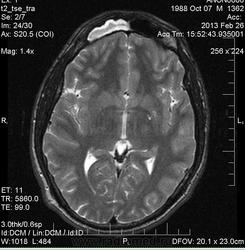

Правосторонний гайморит, фронтит, этмоэдит в фазе выпота. Киста ли это в верхне-медиальных отделах правой в/ч пазухи?

В мае удаляли зуб справа. Беспокоят гнойные выделения из полости носа. На ортопонтограмме со слов пациента без патологии. В области альвеолярного отростка верхней челюсти  справа в области коренных зубов визуализируется зона отека? деструкции?

У товарища похоже, что и фронтит и гайморит справа. Слева утолщенная слизистая. А словам, что на орто норма, можете не верить.

А может быть это аспиргиллема в правой в/ч пазухе?